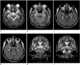

Neurosyphilis

Neurosyphilis refers to infection of the central nervous system in a patient with syphilis. In the era of modern antibiotics the majority of neurosyphilis cases have been reported in HIV-infected patients. [Source: Wikipedia ]